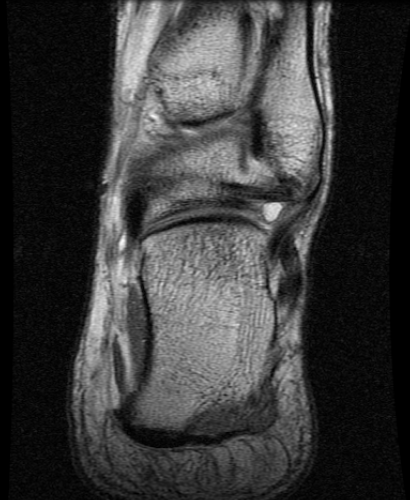

MRI

CFL

PTFL

Deltoid ligament